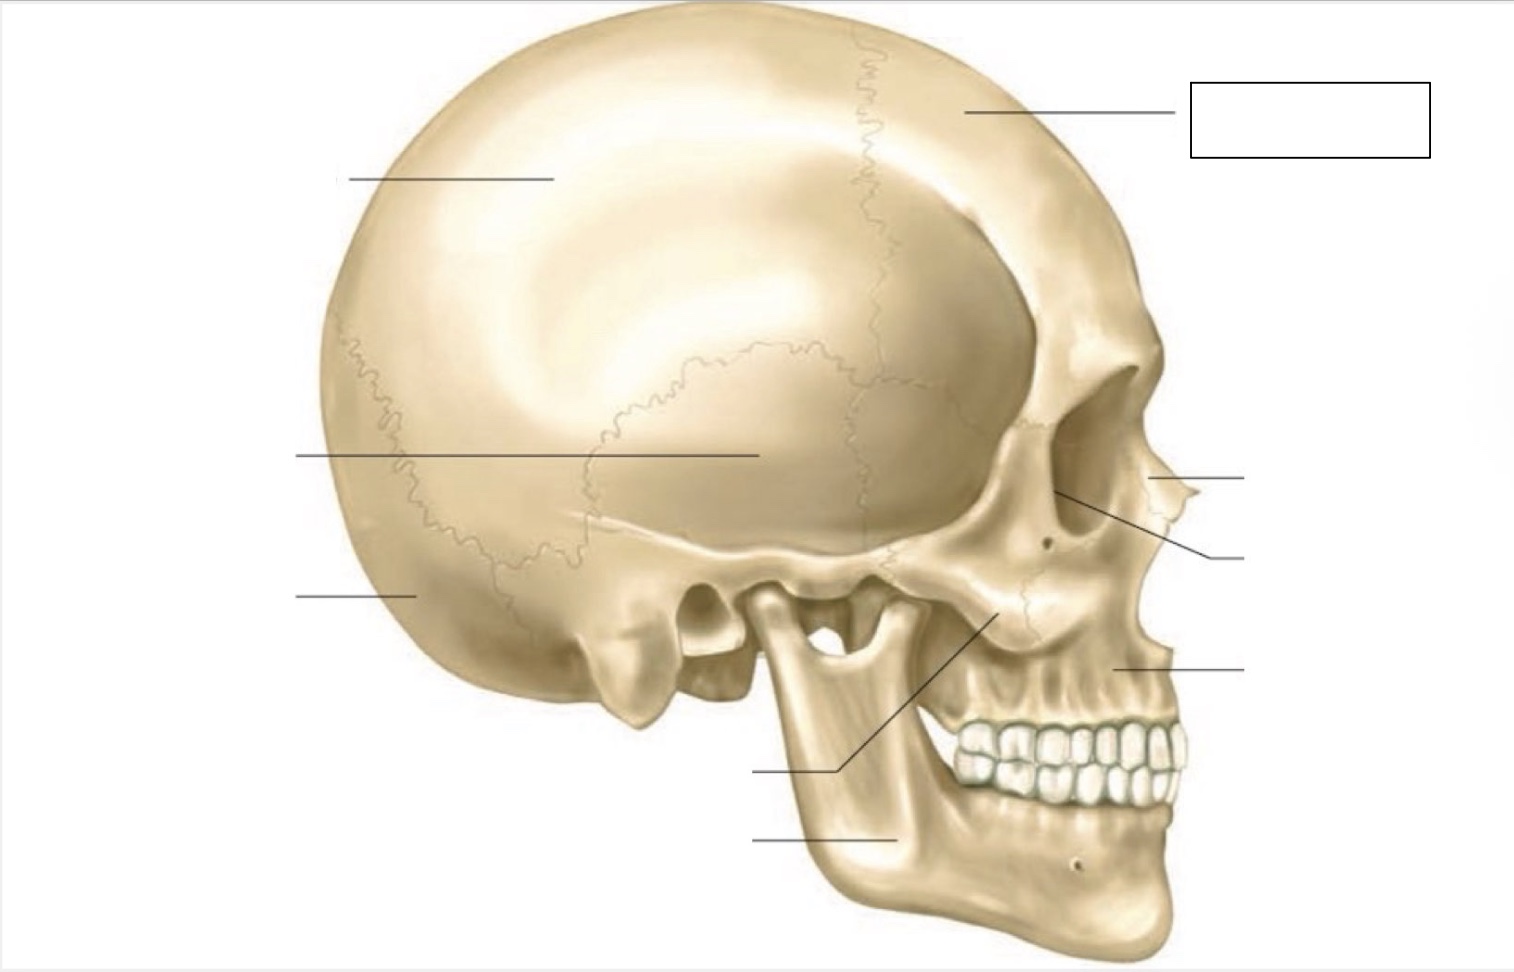

skull

frontal bone

nasal bone

orbit

maxilla

mandible

zygomatic bone

occipital bone

temporal bone

parietal bone